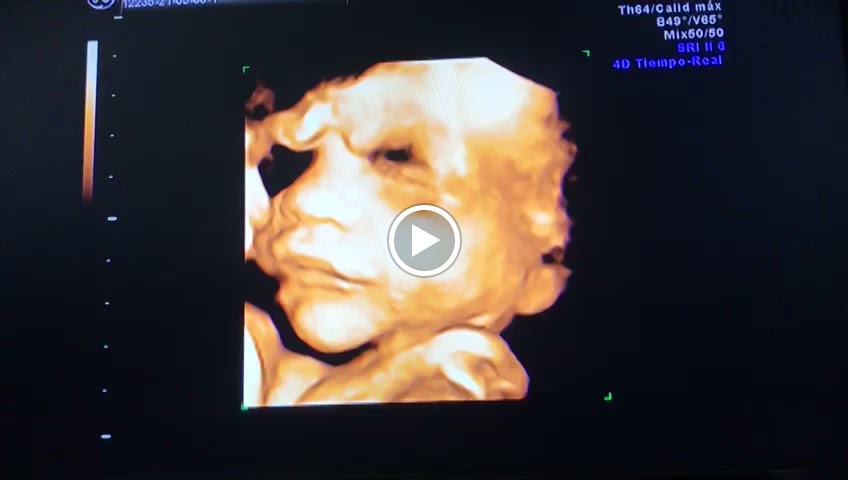

Medical diagnostic imaging center Family practice physician General practitioner

I am a high risk pregnancy and need to have a ultrasound every two weeks. My doctor recommended me to obtain my ultrasound during my visit to Mexico. I called several places to make sure they performed a middle cerebral artery dobbler around the areas and I had no luck. Until I came across Dr. Medinas page. I was able to set up an appointment right away. He was very flexible with his hours. The doctor was very professional and polite. He was very thorough on the ultrasound he took his time and explained everything to us. I was very pleased with his service. I highly recommend him.